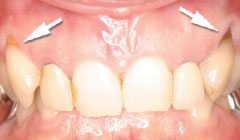

||

| 一見分りませんが、かなり歯周病が進行していました。歯周ポケットの改善や歯槽骨を平坦にして清掃しやすい環境を整えます。数ヶ月、歯肉の盛り上がりを待ってから適合の良いクラウンを被せます。 | ||